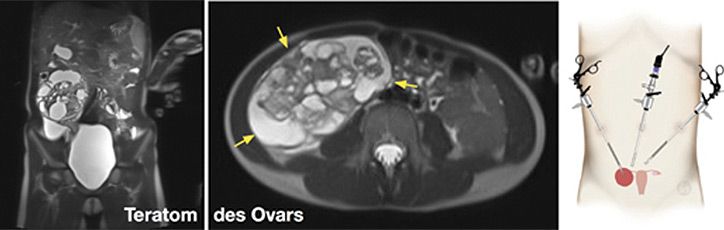

Keimzelltumoren

Diese entsehen aus primordialen Keimellen und betreffen die der (Hoden bzw. Ovarien), kommen aber als sog. extragonadale Keimzelltumoren auch ausserhalb der Gonaden vor. Extragonadale Manifestationen betreffen den Kopf, das die Brust- und Bauchhöhle sowie den Steissbereich. Histologisch unterscheidet man Teratome, Dottersacktumoren, Choriokarzinome, embryonale Karzinome und Mischformen.

Die Behandlungsstrategie für diese Tumoren ist individuell unterschiedlich, beinhaltet jedoch das chirurgische Vorgehen in einem Grossteil der Fälle. Wir führen sämtliche chirurgischen Verfahren bei der Behandlung kindlicher Keimzelltumoren durch, inklusive der minimal- invasiven Chirurgie. Auch die Nachbetreuung entsprechender Patienten nach den Richtlinien der jeweiligen GPOH-Studien findet bei uns statt.